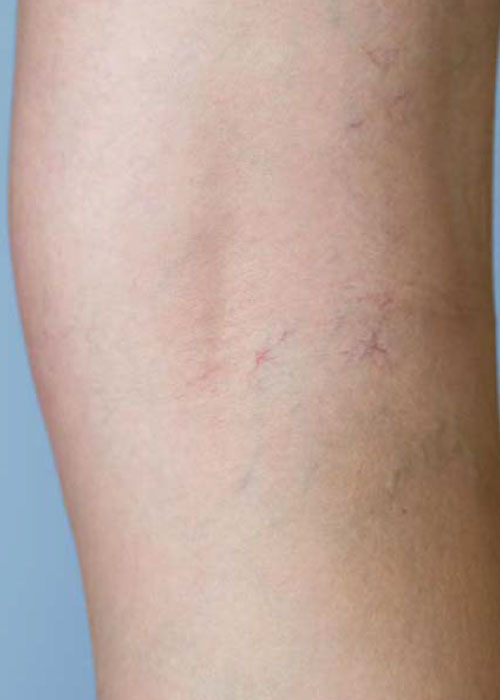

DESCRIÇÃO DO PROBLEMA: VARIZES E TELANGIECTASIAS

As varizes são veias dilatadas e torcidas que geralmente ocorrem nas pernas, resultantes de uma pressão excessiva nas veias, causando um funcionamento inadequado das válvulas venosas. As telangiectasias, por sua vez, são pequenas dilatações dos vasos sanguíneos que se tornam visíveis na superfície da pele, formando manchas vermelhas ou roxas. Ambas as condições estão frequentemente associadas a fatores como: